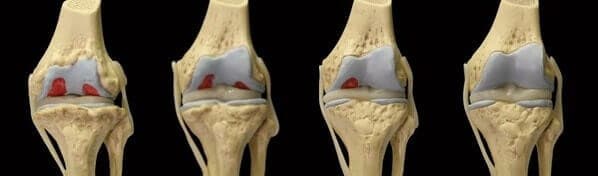

Gracias a su fórmula única, Motion Energy puede hacer frente a cualquier enfermedad articular:

- artritis

- artrosis

- coxartrosis

- osteoartrosis

- osteocondrosis

- osteocondritis

- osteoporosis

- lesiones de menisco

- gonartrosis